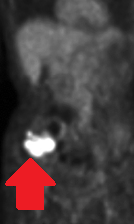

PET Scan. Μεταστατικό καρκίνωμα στη δεξιά υπερώια αμυγδαλή (Ευγενική παραχώρηση Dr. V. Penopoulos).

PET scan ολόκληρου σώματος. Παθολογική πρόσληψη στη δεξιά υπερώια αμυγδαλή (Ευγενική παραχώρηση Dr. V. Penopoulos)